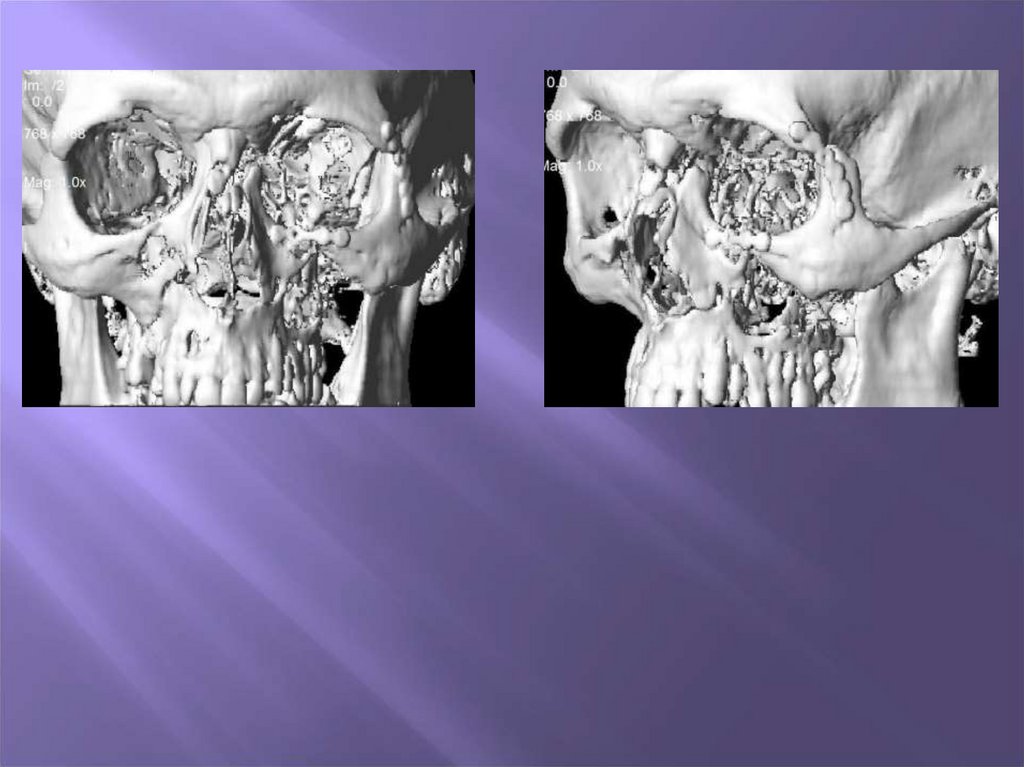

38. Изготовление стереолитографической модели

4. Изготовление стереолитографической

модели